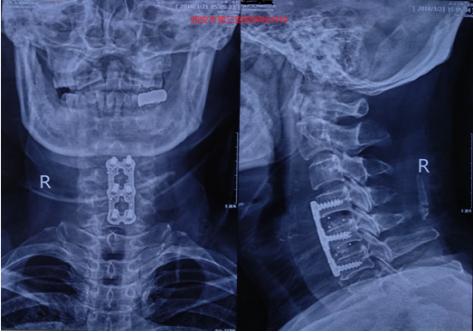

术后颈椎正侧位X片